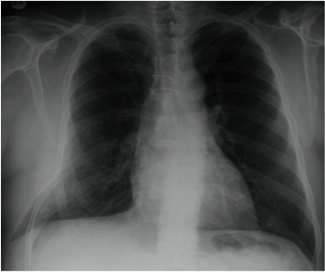

El diagnóstico es clínico y se confirma mediante exámenes complementarios. En la radiografía de tórax, se pueden encontrar hallazgos sugestivos como la protrusión del parénquima pulmonar entre los espacios intercostales que se encuentran aumentados y se visualiza un abombamiento radiolúcido entre las costillas que se sobrepone a los tejidos blandos;25 descrito como visualizar el límite del pulmón más allá de la reja costal («lung beyond the rib» sign). En cambio, cuando la hernia se visualiza frontalmente, puede detectarse un área focal hiperlucente («lucent lung» sign). Las radiografías realizadas en maniobra de Valsalva o espiración pueden aumentar el tamaño de la hernia.27 (Figuras 2-5).

Figura 2.

Signos radiológicos de la hernia pulmonar. “Lung beyond the ribs” sign.

Tomado de: Zia Z, Bashir O, Ramjas GE, Kumaran M, Pollock JG, Pointon K. Intercostal lung hernia: radiographic and MDCT findings. Clin Radiol 2013;68(7):e412-7. http://dx.doi.org/10.1016/j.crad.2012.11.024